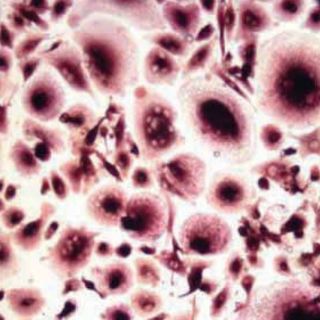

CIUDAD DE MÉXICO (18/AGO/2011).- Los estrógenos, hormonas sexuales femeninas, favorecen la producción de quimiocinas implicados en el desarrollo del cáncer pulmonar en mujeres.

Las quimiocinas son moléculas que normalmente ayudan a las células del sistema inmune a migrar a sitios donde hay una infección, para que puedan llevar a cabo su "trabajo de limpieza".

Sin embargo, si las pertenecientes a un tumor expresan esas moléculas las utilizan para trasladarse a donde hay más quimiocinas.

De esta manera, es favorecida la metástasis.

Hasta ahora, las investigadoras han encontrado que las hormonas femeninas favorecen la expresión de las quimiocinas en el microambiente del tumor, lo que facilita que las células neoplásicas proliferen, migren a otros sitios y hagan metástasis.